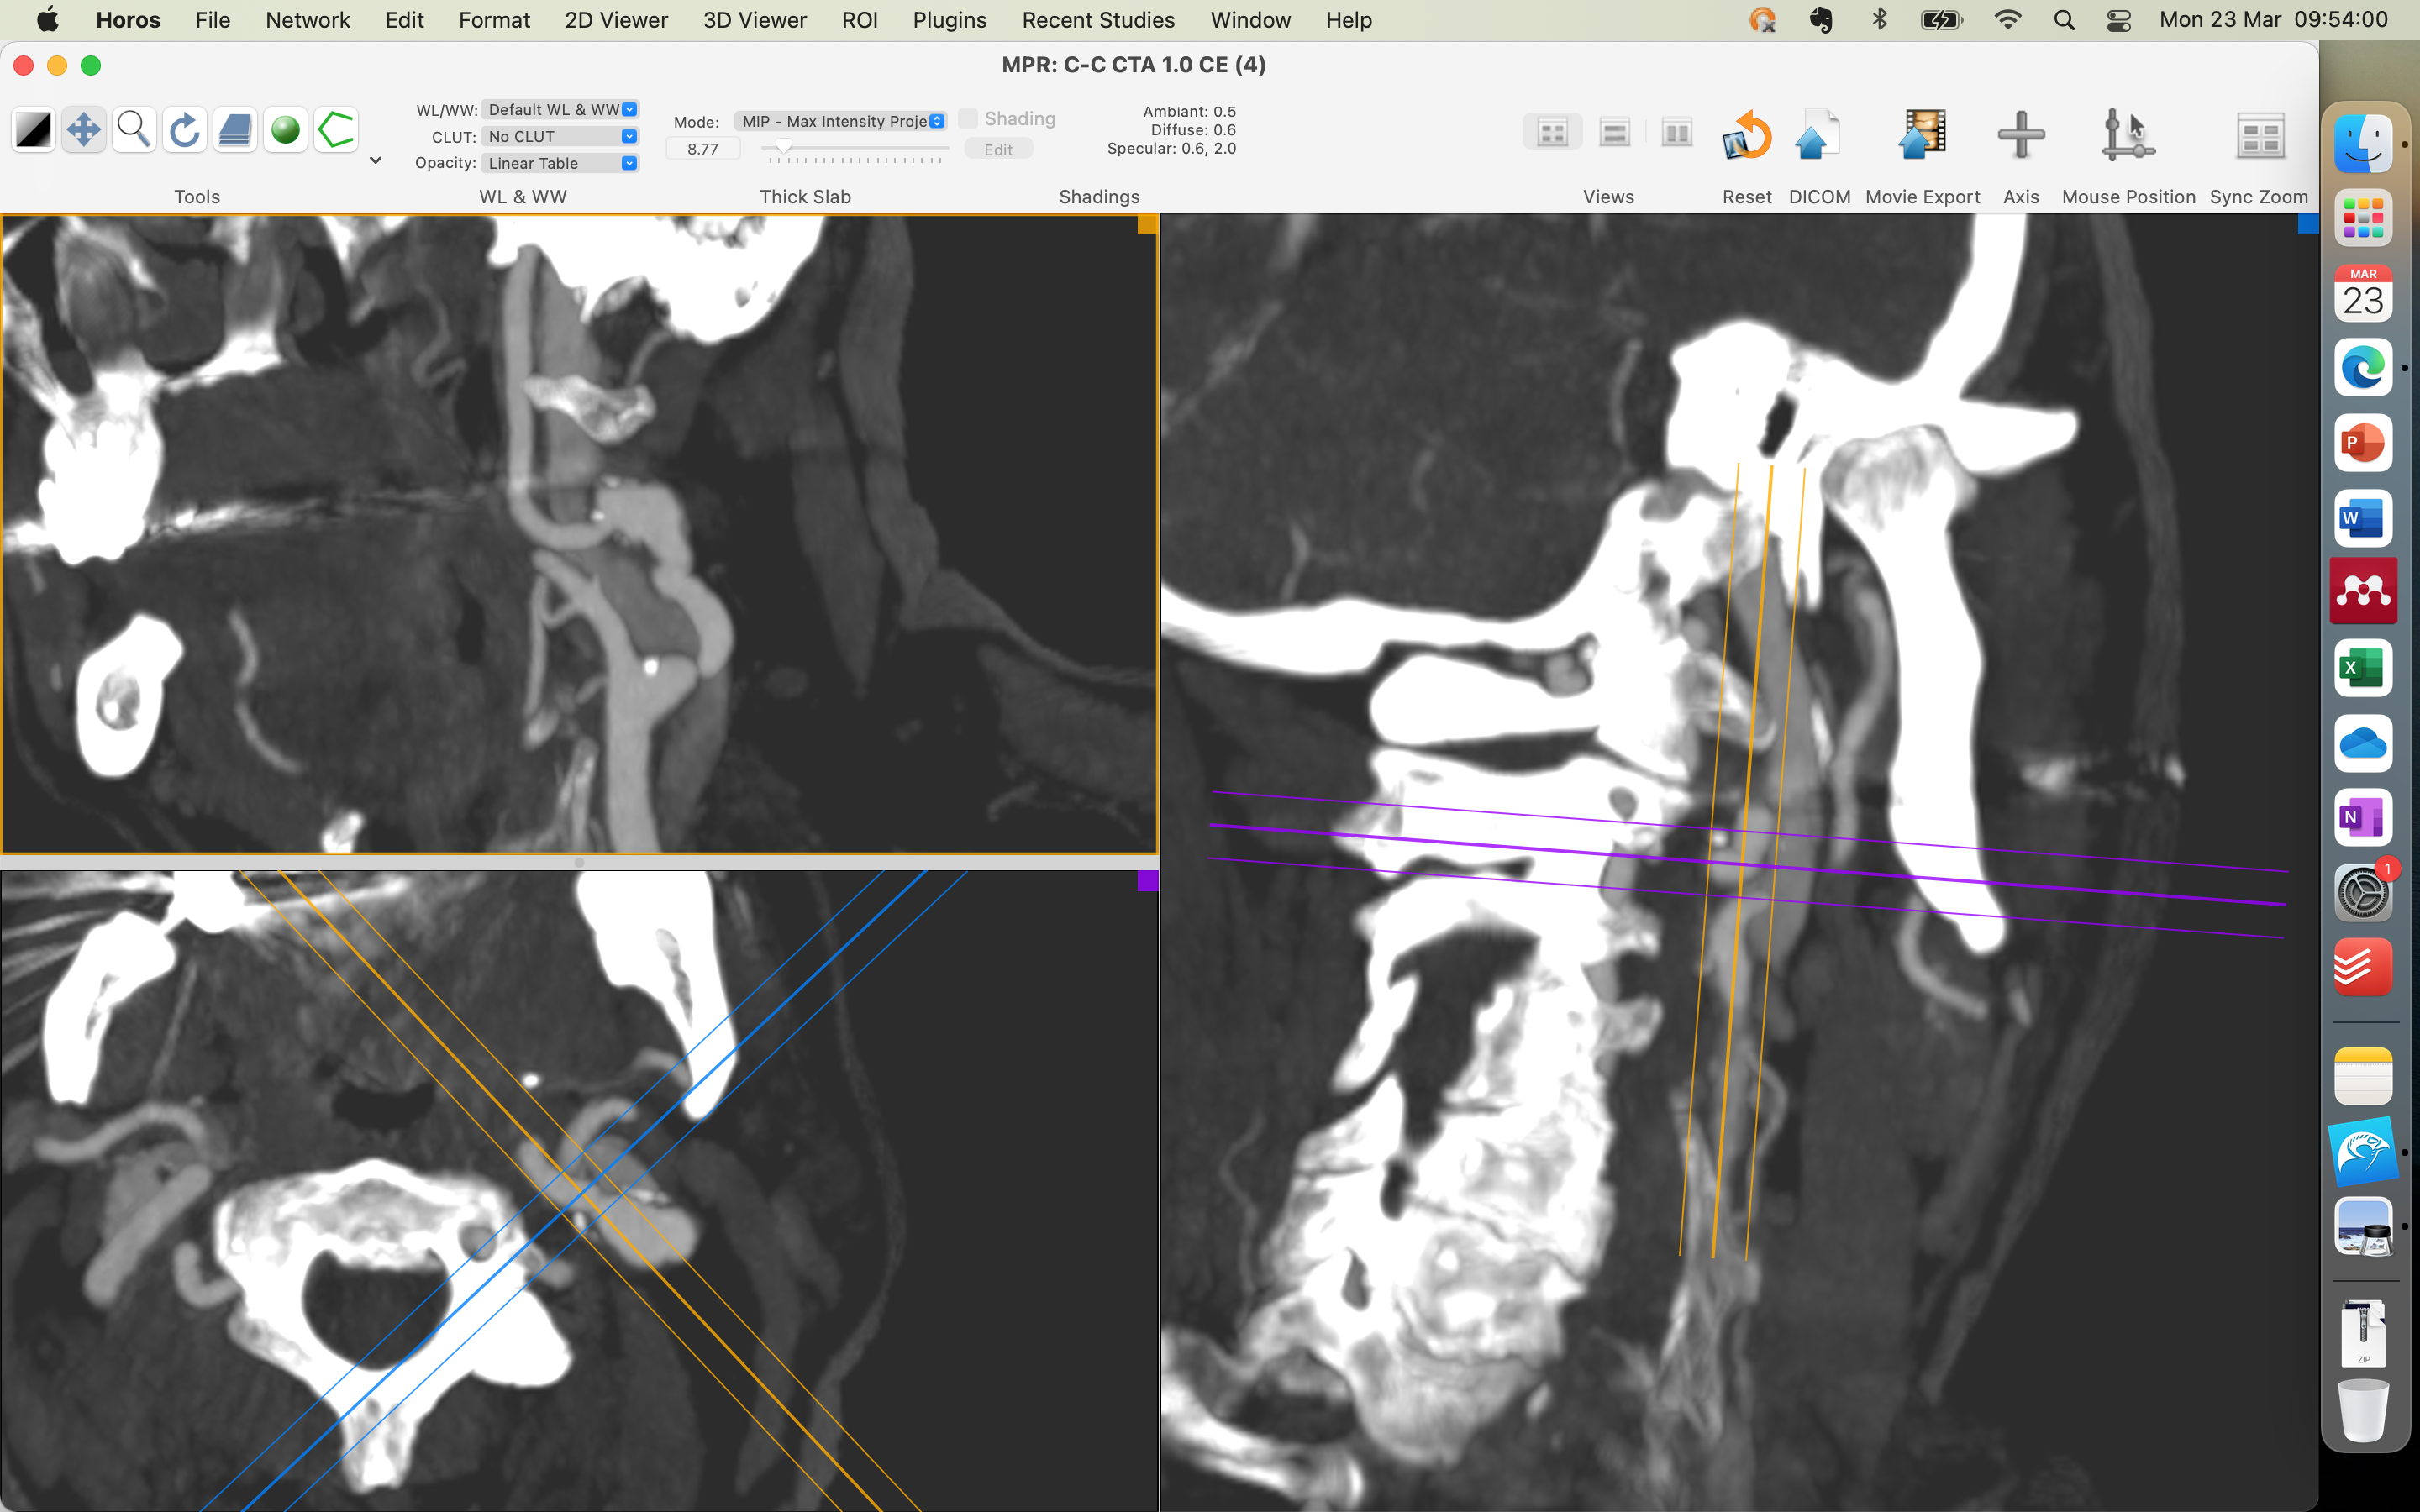

-ANGIOTOMGRAFIA ARTERIALDO CRÂNIO(04/11/2025): PLACAS ATEROMATOSAS PREDOMINANTEMENTE CALCIFICADAS NOS SEGMENTOS INTRACRANIANOS DAS ARTÉRIAS CARÓTIDAS INTERNAS, SEM PROMOVER ESTENOSE. ARTÉRIAS CEREBRAIS ANTERIORES, MÉDIAS E POSTERIORES SEM SINAL DE OCLUSÃO OU ESTENOSE. SEM EVIDÊNCIAS DE MAL FORMAÇÃO ARTERIO-VENOSA OU DILATAÇÕES ANEURISMÁTICAS. IMPRESSÃO DIAGNÓSTICA NO LAUDO: ATEROMATOSE CAROTÍDEA , SEM DETERMINAR ESTENOSES RELEVANTES.

-ANGIO TC ARTERIAL CERVICAL(04/11/2025): IMPRESÃO DX: DOENÇA ATEROMATOSA COM IRREGIULARIDADES/ULCERAÇÕES SUPERFICIAIS NO ARCO AÓRTICO E PRINCIPAIS TRONCOS ARTERIAIS SUPRA-AÓTICOS, SEM ESTENOSE; DOENÇA ATEROMATOSA MISTA NA BIFUCAÇÃO CAROTÍDEA COM IRREGULARIDADES SUPERFICIAIS : CARÓTIDA INTERNA DIREITA: ESTENOSE LEVE(INFERIOR A 50%, CARÓTIDA INTERNA ESQUERDA : ESTENOSE IMPORTANTE NA PORÇÃO PROXIMAL( ACIMA DE 70%). SEGMENTO DE ECTASISA FOCAL NO TERÇO MÉDIO DA CARÓTIDA INTERNA ESQUERDA COM SINAIS DE ACOMETIMENTO´POR DOENÇA ATEROMATOSA.

-DOPPLER DE ARTÉRIAS CAROTÍDEAS E VERTEBRAIS( 22/09/2025): EXTENSA ATEROMATOSE CAROTÍDEA , DESTACANDO AREA DE KINGING NA EMERG~ENCIA DA CARÓTIDA INTERNA ESQUERDA QUE ASSOCIADA A PLACA FIBROCALCIFICADA DETERMINAM ESTENOSE MAIOR QUE 70%.

ESTENOSE DE 90% DE ACIE ASSINTOMATICO, ATEROSCLOSE/FIBRODISPLASIA (ESTENOSE DISTAL AO OSTIO COM DILATACAO DISTAL)

ESTENOSE ACID 60% ASSINTOMATICO

- ENCAMINHO O PACIENTE PARA SANTA CASA DE MARILIA PARA REALIZAR ARTERIOGRAFIA DE CAROTIDAS E VERTEBRAIS PARA DEFINIR SE IRA OU NAO REALIZAR ANGIOPLASTIA/ ENDARECTOMIA,